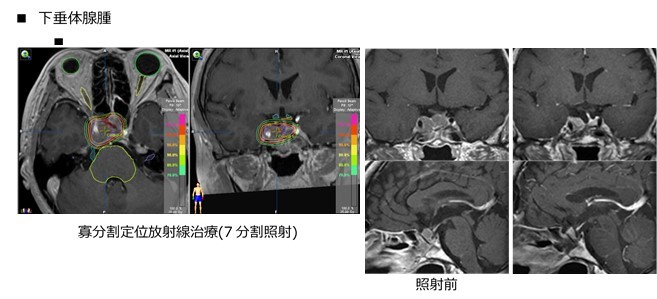

- 良性脳腫瘍

- 髄膜腫、神経鞘腫、下垂体腺腫、頭蓋咽頭腫、血管芽腫、良性神経膠腫、脊索腫、中枢性神経細胞腫、松果体細胞腫など